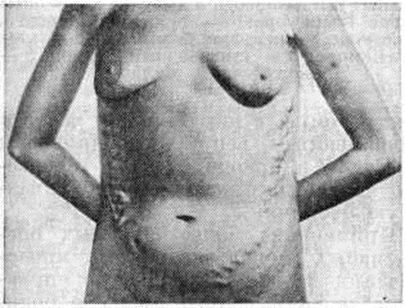

Нередко первым симптомом, выявляющим заболевание (особенно при внепечёночной форме Портальная гипертензия), является случайно обнаруженная увеличенная селезёнка или внезапно возникшее кровотечение из вен пищевода. Больные жалуются на общее недомогание, чувство тяжести в левом подреберье, иногда сопровождающееся болями и повышением температуры, метеоризм, увеличение живота. У больных с асцитом часто выявляются расширенные вены на передней брюшной стенке вокруг пупка (голова медузы) либо по направлению к грудной клетке или надлобковой области (рисунок 2) с характерным при аускультации шумом волчка над ними. Портокавальные анастомозы возникают при внутрипечёночном блоке портальной системы в результате функционирования пупочной вены и обозначаются как синдром Крювелье — Баумгартена (смотри полный свод знаний: Крювелье — Баумгартена синдром). При болезни Киари расширенные вены локализуются чаще по боковым стенкам живота (рисунок 3), на спине и нижних конечностях.

Рис. 3. | ||